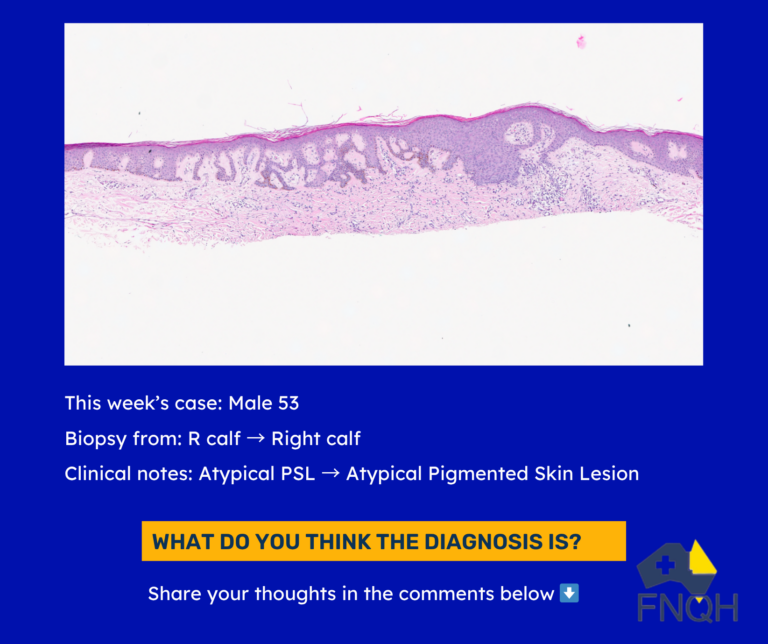

🧑⚕️ Patient

- 53-year-old male

📍 Presentation

- Biopsy from the right calf for assessment of an atypical pigmented skin lesion.

💬 What’s the diagnosis?

- Dermatofibroma